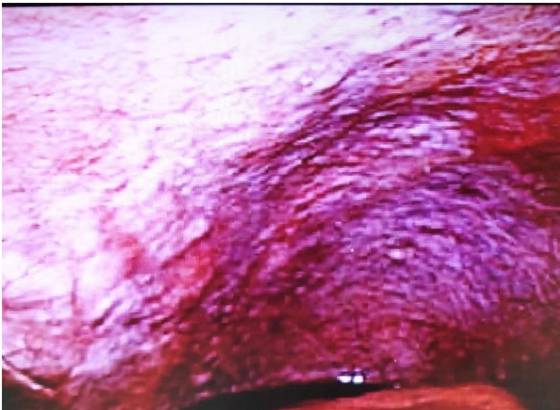

Patients (case 1, 2, 5, and 7) treated by LHIPEC alone were alive with WDPM (case 2, 5, and 7) from 11 to 77 months or without WDPM (Case 1) after 92 months (Table 2). PCI of case 1 at the 1st LHIPEC was 3, but it was 0 at the second laparoscopy, performed 6 months after the 1st LHIPEC. PCI of case 2 at the 1st LHIPEC was 30 (Figure 9), and WDPM was completely disappeared at the 2nd laparoscopy (Figure 10). However, PCI of case 7 was not changed at the 1st LHIPEC (PCI of 36) and 2nd LHIPEC (PCI of 36). PCIs of Case 3 and 4 at the 1st LHIPEC were 15, and 16, and those at the laparotomy became 3 and 13. Accordingly, complete resection could be done in the two cases, and they are alive without recurrence. In contrast, PCIs of case 8 and 9 at the laparotomy were 26 and 23, and those could not be reduced by LHIPEC and IP chemotherapy to the levels to perform complete resection. Additionally, small bowel mesentery in these 2 cases was diffusely involved, Case 8 died of mesothelioma recurrence in pleural cavity and abdominal wall, and the histology showed MPM (Figure 11). Case 9 is alive with mesothelioma recurrence in peritoneal cavity and the pathologic diagnosis was biphasic type of DMPM. Case 5 committed suicide.

Figure 9: Laparoscopic finding of pelvic peritonealsurface Case 2.